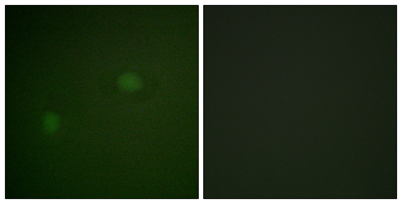

Product name: NPM rabbit pAb

Dilutions: Western Blot: 1/500 - 1/2000. Immunohistochemistry: 1/100 - 1/300. Immunofluorescence: 1/200 - 1/1000. ELISA: 1/20000. Not yet tested in other applications.

Cellular localization: Nucleus, nucleolus . Nucleus, nucleoplasm . Cytoplasm, cytoskeleton, microtubule organizing center, centrosome . Generally nucleolar, but is translocated to the nucleoplasm in case of serum starvation or treatment with anticancer drugs. Has been found in the cytoplasm in patients with primary acute myelogenous leukemia (AML), but not with secondary AML. Can shuttle between cytoplasm and nucleus. Co- localizes with the methylated form of RPS10 in the granular component (GC) region of the nucleolus. Colocalized with nucleolin and APEX1 in nucleoli. Isoform 1 of NEK2 is required for its localization to the centrosome during mitosis.